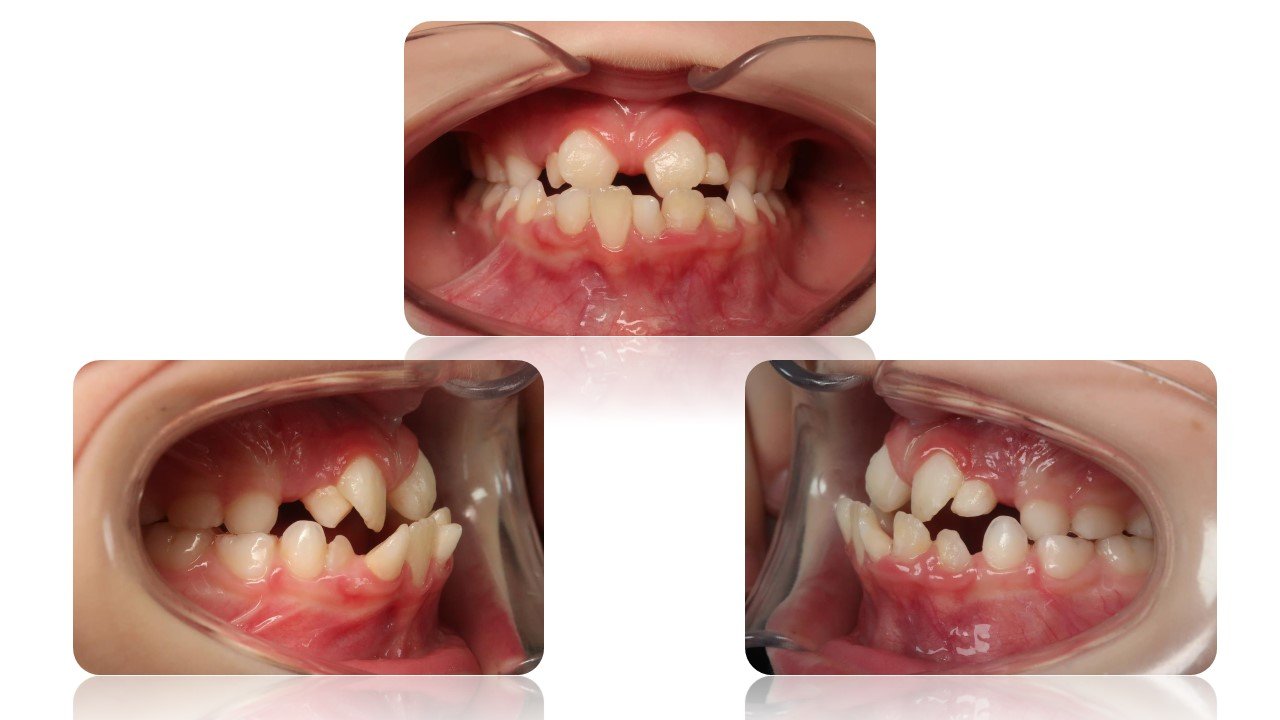

La Classe III Squelettiques

Les classes III squelettiques sont l’expression d’une orientation pathologique du plan occlusal et de la croissance faciale.

L’orthodontie systémique permet d’appréhender cette pathologie par l’analyse des latéralités mandibulaires.

Le traitement qui en découle est donc fonctionnel et stable car il permet non pas seulement une protraction du maxillaire mais une réorientation complète de celui-ci. Cette prise en charge permet de retrouver une proprioception maximale du prémaxillaire dans la mastication, gage de stabilité à long terme.